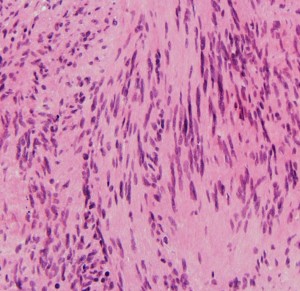

細胞核の柵状配列 (矢印 nuclear palisading). HE x200

画像をクリックすると拡大します

隣り合う細胞核の柵状配列 nuclear palisade arrangement (palisading) は,髄膜腫との鑑別での大切な所見です。